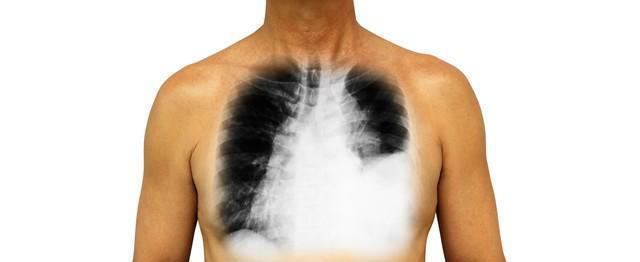

肺癌常被比作“隐秘的刺客”,因为它在初期往往悄无声息,许多患者直到病情恶化到晚期,才惊觉情况不妙。更让人意外的是,肺癌的不仅会影响呼吸系统,甚至会通过血液循环等方式影响全身,双腿常常是最早发出信号的部位之一。今天我们就来看看,双腿早早发出的四个肺癌预警信号,希望每个人都能对这些症状提高警惕,及时检查。

肺癌的早期症状常常容易被忽视,尤其是像张先生这样认为双腿无力只是老年人正常退化的表现,而非癌症的警告信号。但其实,早期肺癌是有办法治疗的。根据医学研究,如果早期就发现肺癌并进行治疗,五年内生存下来的机会能有50%以上,可要是拖到晚期才发现,那五年生存率就只有5%到10%了。所以说,早点去做检查,早点发现问题,就能大大提高治好的机会。

肺癌并非无声无息地潜伏在体内,它往往通过一些身体的反应来提醒我们,只是这些信号常常被忽视。双腿作为血液循环的远端,最早感知到肺癌的侵袭,如果你或你身边的人出现了双腿无力、肿胀、皮肤变色或走路疼痛等症状,千万不要掉以轻心。毕竟,尽早察觉并予以治疗,方为战胜癌症的关键所在。其重要性不言而喻,唯有如此,方能在抗癌之战中占据优势。